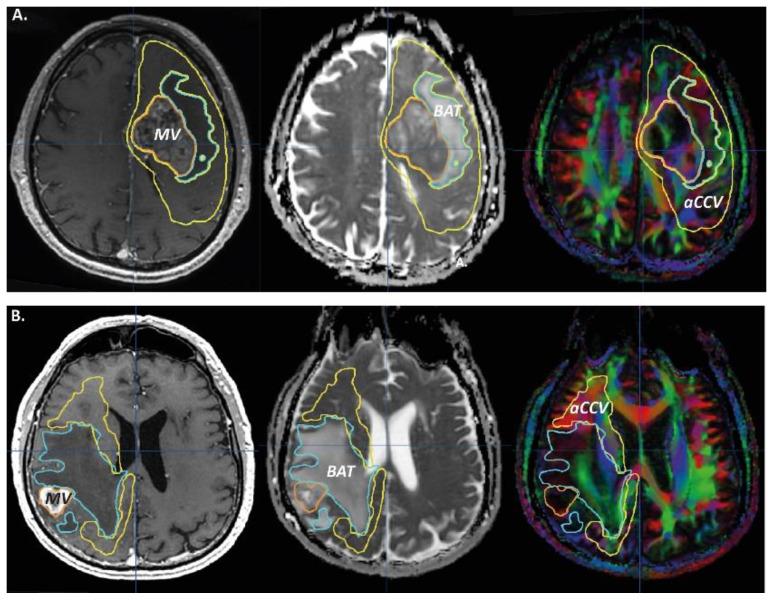

(1) Background: Glioblastoma multiforme (GBM) shows complex mechanisms of spreading of the tumor cells, up to remote areas, and little is still known of these mechanisms, thus we focused on MRI abnormalities observable in the tumor and the brain adjacent to the lesion, up to the contralateral hemisphere, with a special interest on tensor diffusion imaging informing on white matter architecture; (2) Material and Methods: volumes, macroscopic volume (MV), brain-adjacent-tumor (BAT) volume and abnormal color-coded DTI volume (aCCV), and region-of-interest samples (probe volumes, ipsi, and contra lateral to the lesion), with their MRI characteristics, apparent diffusion coefficient (ADC), fractional anisotropy (FA) values, and number of fibers (DTI fiber tracking) were analyzed in patients suffering GBM ( = 15) and metastasis ( = 9), and healthy subjects ( = 15), using ad hoc statistical methods (type I error = 5%) (3) Results: GBM volumes were larger than metastasis volumes, aCCV being larger in GBM and BAT ADC was higher in metastasis, ADC decreased centripetally in metastasis, FA increased centripetally either in GBM or metastasis, MV and BAT FA values were higher in GBM, ipsi FA values of GBM ROIs were higher than those of metastasis, and the GBM ipsi number of fibers was higher than the GBM contra number of fibers; (4) Conclusions: The MV, BAT and especially the aCCV, as well as their related water diffusion characteristics, could be useful biomarkers in oncology and functional oncology.

(1) 背景:多形性胶质母细胞瘤(GBM)显示出肿瘤细胞扩散的复杂机制,甚至可以扩散到远处,而这些机制仍知之甚少,因此我们专注于肿瘤和邻近病变的大脑的 MRI 异常,直到对侧半球,特别关注张量扩散成像提供的白质结构信息;(2) 材料和方法:体积、宏观体积(MV)、肿瘤旁(BAT)体积和异常彩色编码 DTI 体积(aCCV),以及感兴趣区样本(探头体积,同侧和对侧病变),及其 MRI 特征、表观扩散系数(ADC)值、各向异性分数(FA)值和纤维数量(DTI 纤维跟踪)在 GBM(=15)和转移瘤(=9)和健康受试者(=15)中进行分析,使用特定的统计方法(错误类型 I = 5%);(3) 结果:GBM 体积大于转移瘤体积,GBM 的 aCCV 更大,而转移瘤的 BAT ADC 更高,转移瘤的 ADC 向心性降低,GBM 和转移瘤的 FA 向心性增加,MV 和 BAT FA 值在 GBM 中更高,GBM ROI 的同侧 FA 值高于转移瘤,而 GBM 的同侧纤维数量高于对侧纤维数量;(4) 结论:MV、BAT 特别是 aCCV 及其相关的水扩散特征可能是肿瘤学和功能肿瘤学的有用生物标志物。